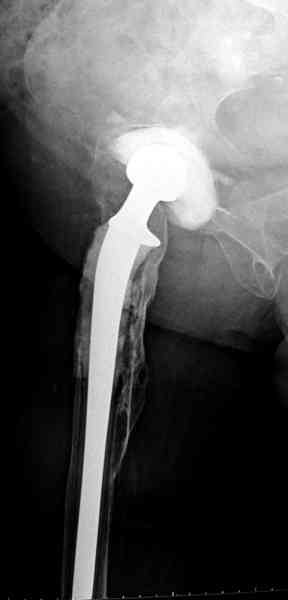

Наглухо ушитая рана с дренажом зажила первично, после чего с больной потерял контакт, и только недавно, через 8 лет я осмотрел её. Она без проблем нагружает на конечность и передвигается с помощью трости. От окончательной операции по реконструкции отказывается, довольная результатом.

Имеются литературные данные, когда спейсер держали не более 6 месяцев, но этот случай бьет все рекорды, может быть для наших людей, обременных финансовыми трудностями, нужна другая шкала оценки сроков нахождения спейсеров.

№3-6 снимки с осложнением

и последние снимки.